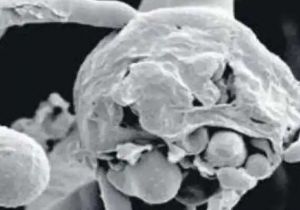

मेडिकल में ब्लैक फंगस के बीच व्हाइट फंगस के मिले दो संदिग्ध

21 May, 2021 06:36 PM IST | SAMIKSHASAGAR.COMजबलपुर कोविड संक्रमण के बीच सामने आएजानलेवा ब्लैक फंगस की बीमारी केपीड़ितों की संख्या जहां लगातारबढ़ती...